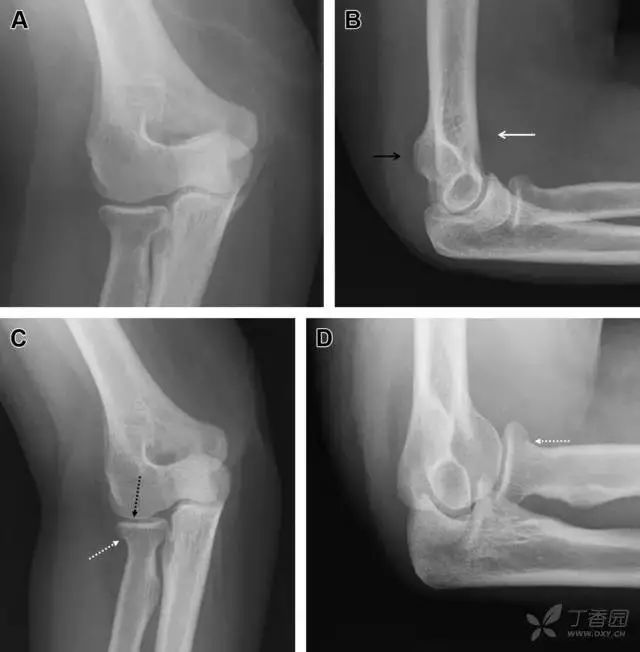

无移位的桡骨头/颈骨折

多发生于摔倒时,手掌撑地,受到轴向、外翻应力所致。常规的前后位片容易漏诊,常需加拍内斜位、外斜位、桡骨头-肱骨小头位片。后脂肪垫可见(位于鹰嘴窝内,一般不可见)和/或前脂肪垫抬高常提示骨性损伤。

图 2 桡骨头骨折。前后位(A)和侧位(B)片示后脂肪垫抬高(黑色箭头),前脂肪垫抬高(白色箭头),呈「帆船征」,其它表现正常;外斜位(C)和桡骨头–肱骨小头位(D)示桡骨头关节内骨折线(虚线黑箭头)累及桡骨颈(虚线白箭头)